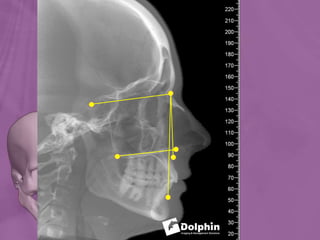

Lateral Cephalogram

Ortho radio diagnosis

 Although the cephalometric radiograph in standard

lateral projection was introduced into orthodontics

during 1930s, the method has become routine in recent

years.

 Today cephalometric analysis has firmly taken place in

dentofacial diagnostic procedures.

uses

1. Assessement of the facial

skeleton

2. Relationship of the jaw

bases

3. Relationship of the axial

inclination of incisors

4. Assessment of the soft

tissue morphology

5. Growth pattern and

direction

6. Localization of the

malocclusion

7. Treatment possibilities and

limitations.

Cephalometrics is used in three major areas:

 Morphological Analysis: By evaluating the

sagittal and vertical relations of dentition,

facial skeleton and soft tissue profile.

 Growth Analysis: By taking two or more

cephalograms at different time intervals and

comparing the changes.

 Treatment Analysis: By evaluating alterations

during and after therapy.